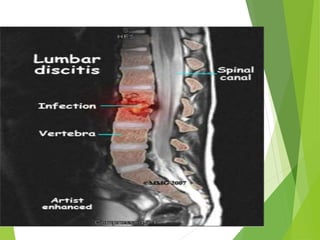

 Discitis or diskitis is an infection in the intervertebral

disc space that affects different age groups, but usually

spontaneously affects children under 8 years of age.

 Nonetheless, discitis occurs post surgically in

 Discitis ordiskitis is an infection in the intervertebral disc space that affects different age groups, but usually spontaneously affects children under 8 years of age.  Nonetheless, discitis occurs post surgically in approximately 1-2 percent of patients after spinal surgery.

Symptoms  severe backpain, leading to lack of mobility.  Some very young children may refuse to walk and arching of the back is possible.  In post-operative situations, the symptoms occur within a week and result in severe low back pain or neck pain (depending on the surgical location).  If untreated, the discitis may resolve on its own, cause a chronic low grade infection, or progress to osteomyelitis and possibly even an epidural abscess.